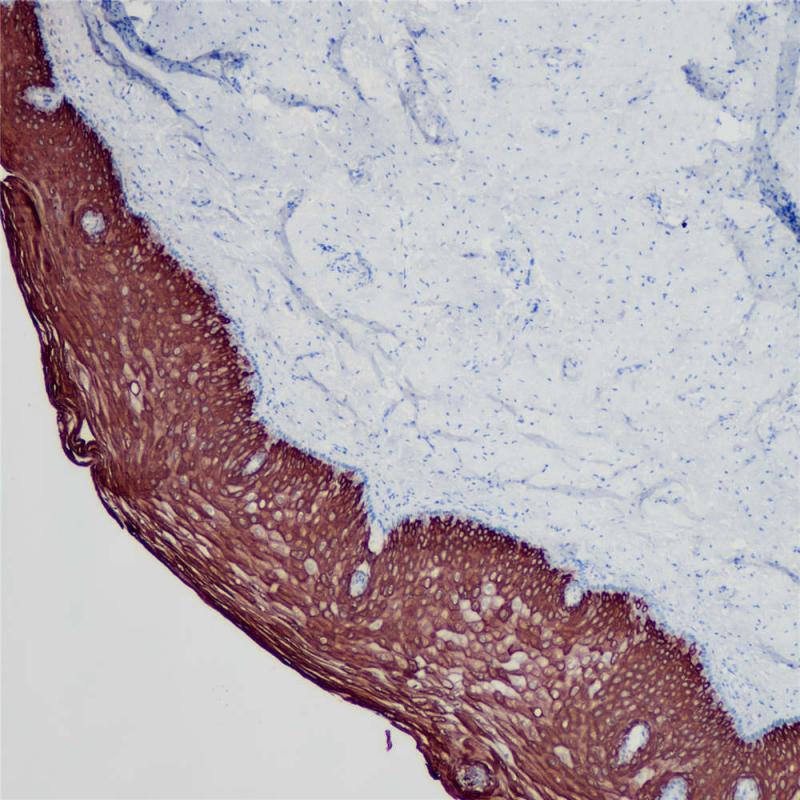

PAX-2是PAX转录因子家族成员之一,与PAX-8一起参与肾脏器官的形成。在非肿瘤组织中,PAX-2表达于肾小球壁上皮细胞,肾集合管细胞,萎缩的肾小管细胞,卵巢表层上皮细胞,输卵管,子宫颈内膜,子宫内膜。在原发性肿瘤中,PAX-2主要出现于肾细胞癌,肾原性肿瘤。近来的调查表明,PAX-2可作为有效的免疫组织化学标记物,有助于诊断肾上皮细胞瘤以及一些妇科肿瘤。

阳性对照

细胞核